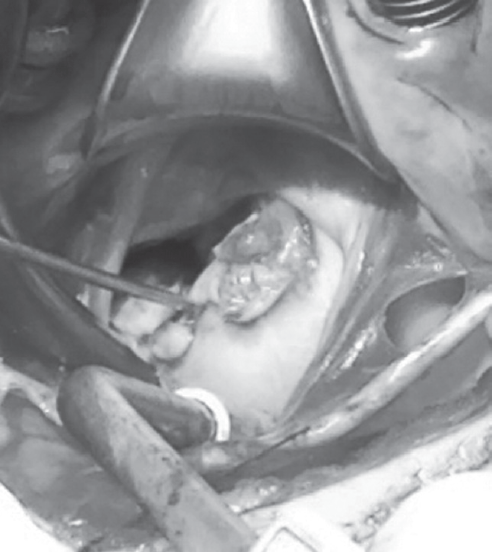

The optimal time for surgery on the heart valves in patients with active infectious endocarditis (IE) is still controversial. It is a well known fact that cerebral, coronary or renal thromboembolism is the most common cause of death in patients with left-sided IE. Thromboembolism can develop before the appearance of clinical manifestations of the destruction of the valvular apparatus of the heart. Currently, early surgical intervention is considered as the most effective method of treatment of many forms of active left-sided IE. Early surgery involves performing surgical correction until the completion of a full antibiotics course. We present the clinical case of early surgical correction of the patient (A., 16 years) with mitral valve infectious endocarditis. The disease was acute, with recurrent embolisms to the right kidney with infarction and to the left clavicle with osteomyelitis. Surgical intervention was performed as a matter of urgency; surgical access – right-sided anterolateral thoracotomy. The girl was operated on the 4th day of the hospitalization to our hospital. However, time of treatment was lost at the prehospital stage and rapid mitral valve destruction did not allow to repair the valve. Therefore, the mitral valve replacement was performed. The postoperative period was favorable. On the 3rd day after the operation, the girl was transferred to the cardiology department. On control ECHO after 3 years: myocardial contractile function is good, EF 65%, the function of the MV prosthesis is not impaired.